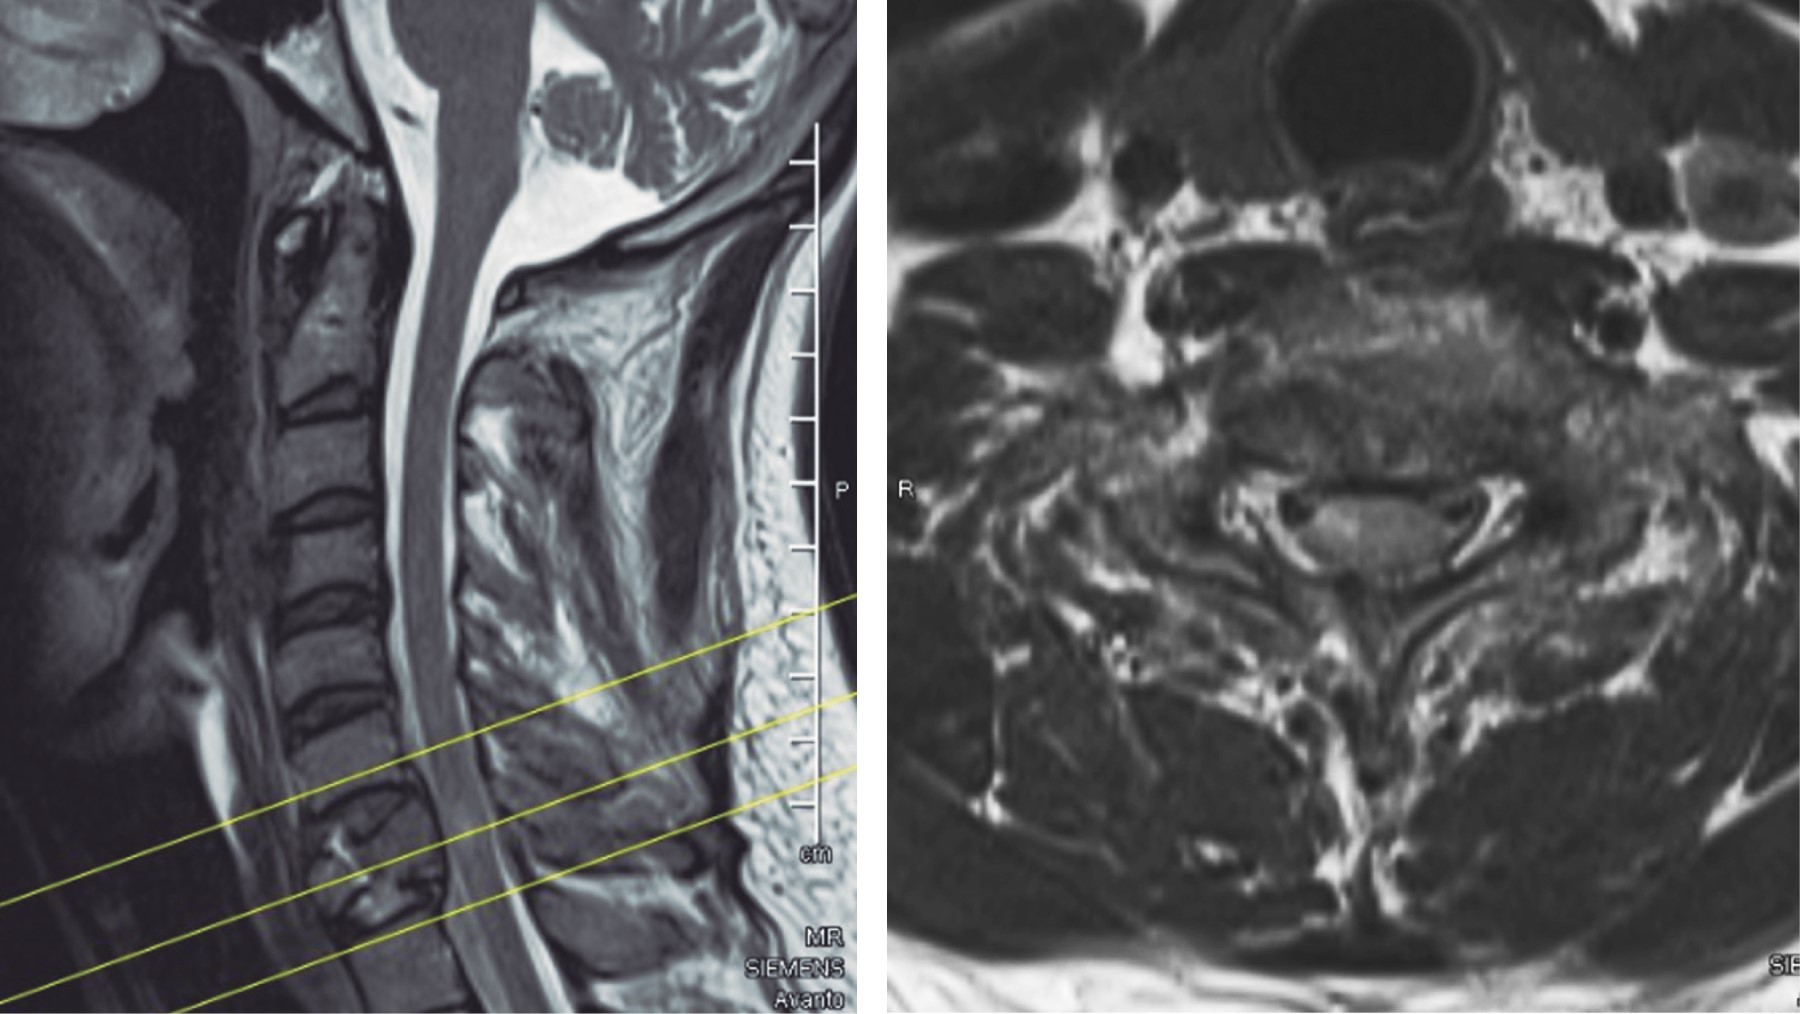

Se presenta el caso de un paciente masculino de 33 años de edad, sin comorbilidades, que acude al servicio de urgencias por presentar cervicalgia de dos semanas de evolución posterior a un accidente en motocicleta. Las radiografías iniciales tomadas en el hospital de primera atención no fueron valorables para diagnóstico; se toman radiografías y tomografía axial computarizada (TAC) de columna cervical (Figuras 1, 2 y 3), diagnosticando fractura de C1 y C7 donde se observa fractura por compresión de C7 AO B2 y C1 con fractura de arco anterior y posterior izquierdo con desplazamiento coronal > 7 mm de la masa lateral izquierda. En la resonancia magnética T2 axial, se observa lesión del ligamento transverso. En resonancia magnética simple se observa fractura de cuerpo vertebral de C7, con compromiso de conducto raquídeo

y lesión de las estructuras posteriores (Figura 4). Se realizó tratamiento quirúrgico consistente en abordaje cervical posterior, colocación de tornillos poliaxiales a masas laterales y reducción en C1 con barra moldeada transversa, instrumentación a masas laterales de C6 C7 transpedicular T1, laminectomía C7, abordaje cervical anterior corpectomía C7, colocación de malla con injerto óseo autólogo y placa cervical anterior (Figuras 5 y 6). La cirugía fue realizada en posición prono con estabilización de la cabeza. Se realizó una incisión media, los músculos paravertebrales fueron retraídos para exponer el arco posterior de C1 y apófisis espinosas de C6 C7 T1. La raíz nerviosa y arteria vertebral fueron identificadas y protegidas para evitar alguna lesión. Durante la disección, se localiza el plexo venoso de C1 C2, realizando hemostasia mediante compresión presentando sangrado considerable que; sin embargo, fue controlado. La unión del arco posterior con la masa lateral se identificó fácilmente por el trazo de fractura, pudiendo identificar y delimitar la masa lateral. El punto de entrada se localizó 3 mm lateral al término del arco posterior. Se insertaron bilateralmente dos tornillos poliaxiales número 4.0 × 22 mm con una angulación medial de 20o y superior de 30o. La fractura se redujo a visión directa, aproximando los tornillos y fijándolos con una barra moldeada bajo control fluoroscópico. Posteriormente se realiza instrumentación a masas laterales de C6 C7 y transpedicular en T1, laminectomía de C7 y colocación de dos barras moldeadas, la herida se cierra por planos y se coloca al paciente en decúbito supino; se realiza abordaje cervical anterior izquierdo, corpectomía de C7 y colocación de placa cervical anterior, se sutura por planos con colocación de drenaje, el cual se retira a las 48 horas. El tiempo de cirugía fue de 3:50 horas con sangrado de 1,000 cm3. El paciente fue extubado sin complicaciones y ningún déficit neurológico. Se da de alta a las 72 horas postquirúrgicas con uso de collarín tipo Aspen por seis semanas.